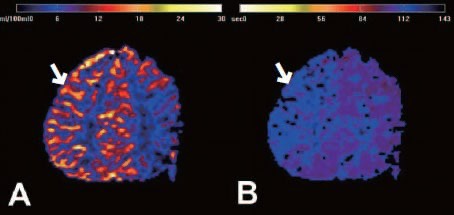

② 간접 우회술(Indirect bypass)

• 근육이나 막 조직을 뇌 표면에 붙여 그 조직에서 자라는 새로운 혈관이 뇌를 공급하도록 유도 • 소아에서 많이 사용

• 혈류 증가 효과가 나타나기까지 수개월이 필요합니다.

③ 혼합 우회술(Combined bypass)

• 직접 + 간접 방법을 동시에 시행하는 방식

• 빠른 효과 + 장기 안정성을 동시에 노릴 수 있는 방법입니다.